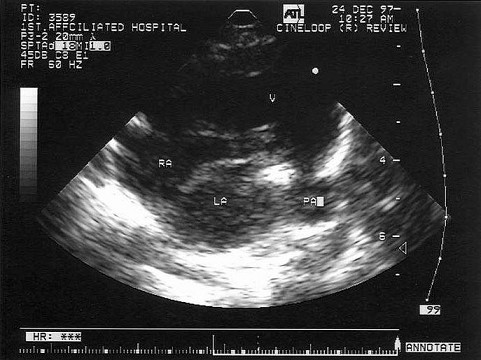

[单选题]该病例最有可能诊断()A.肺静脉畸形引流B.上腔静脉型房缺C.Ⅱ孔型房缺D.卵圆孔重开E.下腔静型房缺

[单选题]该病例最有可能诊断()A.心包炎并心包积液B.心衰C.心包缩窄D.心包填塞E.胸腔积液

[单选题]该病例最有可能诊断()A.肺动脉内径增宽B.动脉导管未闭C.肺动脉瓣狭窄D.肺动脉瓣关闭不全E.右室流出道狭窄